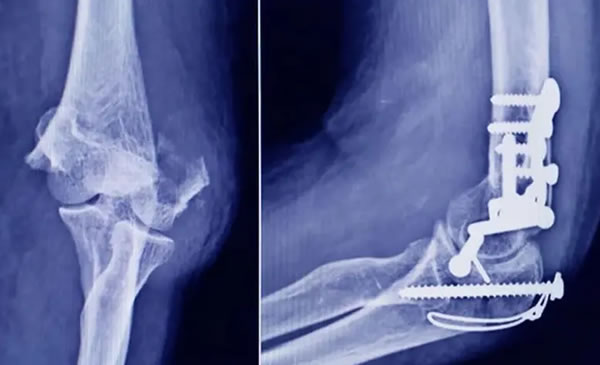

Según detalló la ANMAT, el dispositivo corresponde a un tornillo tipo “twist-off” (o snap-off), utilizado en cirugía traumatológica para fijar pequeños fragmentos óseos y realizar osteotomías o fusiones en pies, tobillos, manos y muñecas.